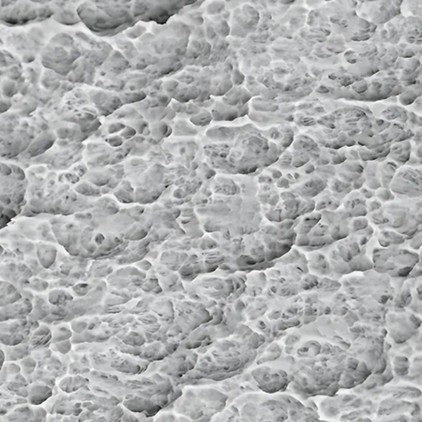

Bề mặt SB/LA độc quyền

Bề mặt Implant Ritter tạo ra sự khác biệt về bề mặt lớn, cho phép Protein huyết tương và máu được hấp thụ mạnh vào các vi lỗ của implant ngay sau khi cấy ghép.

Công nghệ sb/la độc quyền

Công nghệ SB/LA độc quyền (thổi cát hạt lớn và ăn mòn axit) được Ritter thiết kế để đẩy nhanh quá trình tích hợp xương của Implant và tối ưu hóa quá trình lành thương bằng cách mang lại cả lợi thế về mặt cơ sinh học và sinh học. Quá trình này, sử dụng các hạt thô hơn trên công nghệ xử lý bề mặt SLA, tạo ra các vết mài mòn vi mô từ 1-5 µm và các vết mài mòn vĩ mô từ 20-40 µm trên bề mặt. Những vết mài mòn này tạo ra một cấu trúc đa tầng giúp tăng cường sự bám dính của nguyên bào xương (tế bào xương).

Ngay sau khi đặt Implant bề mặt tạo ra các khoảng trống lớn cho phép Protein huyết tương và máu được hấp thụ mạnh mẽ vào các vi lỗ của Implant. Nó cũng tăng cường hoạt động của tế bào xương bằng cách cung cấp độ nhám bề mặt đồng đều hơn.

Độ nhám vi mô và vĩ mô rộng hơn

Bề mặt SB/LA cung cấp độ nhám rộng hơn ở cả cấp độ vi mô và vĩ mô. Độ nhám bề mặt từ 1-5 µm ở cấp độ vi mô và 20-40 µm ở cấp độ vĩ mô cho phép các tế bào xương liên kết chặt chẽ và nhanh hơn với bề mặt.

Tăng tỷ lệ tiếp xúc xương

Bề mặt SB/LA hỗ trợ sự ổn định lâu dài bằng cách tăng tỷ lệ tiếp xúc giữa implant và xương (tiếp xúc xương với implant, BIC).

Khả năng tương thích sinh học

Bề mặt SB/LA được phát triển để tối ưu hóa khả năng tương thích sinh học. Nó cung cấp bề mặt thuận lợi hơn cho các tế bào xương và giảm nguy cơ biến chứng như viêm quanh implant.

Tỷ lệ tích hợp xương sớm

Bề mặt SB/LA thúc đẩy quá trình lành thương sớm của mô xương xung quanh implant. Các nghiên cứu đã chỉ ra rằng hoạt tính sinh học của bề mặt SB/LA cao hơn bề mặt SLA.

Độ đồng nhất bề mặt

Bề mặt SB/LA có cấu trúc nhám đồng đều hơn nhờ lớp oxit titan ưa nước được tạo ra. Điều này làm tăng cả độ ổn định cơ học và khả năng tương thích sinh học.

Tỷ lệ thành công dài hạn

Implant với bề mặt SB/LA mang lại tỷ lệ thành công lâm sàng lâu dài cao hơn. Đây là một lợi thế đáng kể, đặc biệt là trong các trường hợp khó hoặc bệnh nhân có mật độ xương thấp.